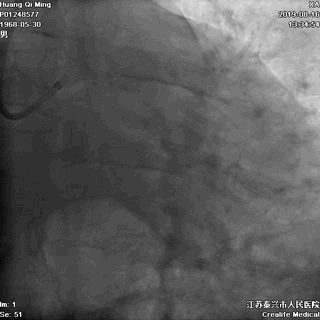

LAD PCI过程

导丝通过病变抵达血管远段

8atm,2.0*20球囊行PTCA

8atm,2.0*10 切割球囊对斑块进行切割

16atm,NC球囊对斑块进行预处理

2.0*25 药物洗脱球囊,8atm*60秒释放药物

2.5*25 药物洗脱球囊,8atm*60秒释放药物

术后即刻效果满意